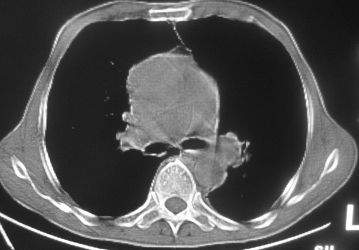

以下是引用卜一在2007-10-7 9:38:00的发言:[br]左下肺胸膜下团片影,内见含气支气管像,临近胸膜未见增厚。多考虑:1 左下肺炎症,建议消炎后复查!2 不除外肺隔离症合并感染!